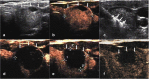

Methods: This retrospective study evaluated 194 non-functioning solid benign TNs of 103 patients. The TNs were categorized as small (≤5 ml), medium (5.1 to 13 ml), intermediate (13.1 to 30 ml) and large (over 30 ml) according to the initial volume of TNs before ablation. Clinical evaluation and contrast-enhanced ultrasound (CEUS) were carried out before ablation and the follow up at 1, 3, 6 months and every 6 months after ablation. All patients were asked to assess the cosmetic score (1-4 scores) and symptom score (0-10 scores) before ablation and every follow up after ablation.

Results: All patients underwent RFA without any major complications. The mean treatment sessions were 1.5 ± 0.6. 98 nodules required a single session (98/194, 50.5%), 87 required two sessions (87/194, 44.9%), 9 required three sessions (9/194, 4.6%). The average follow up months were 16.3 ± 5.6 (range, 6-24 months) and no nodule regrew in our study. After RFA treatment, the TNs volume significantly decreased (P < 0.001). The small group of nodules shrunk larger compared to the medium, intermediate and large groups (P < 0.001). Cosmetic signs and pressure symptoms were significantly improved, particularly in the intermediate and large groups (P < 0.05).